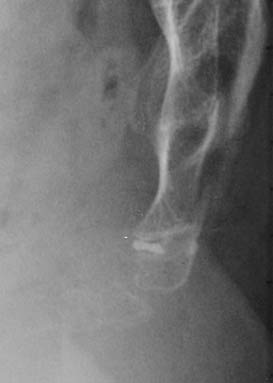

Below are some more common cases of calcifications of the coccygeal discs.

cases #6 to 11

Case #6: permanent calcification of the intercoccygeal disc

Case #7: intradiscal calcification

Case #8: anterior calcification

Case #9: A strange image. I presume it is a calcified hematoma, but I am not sure

Case #10 and 11 : Intradiscal calcification. In both cases, the lower disc was the source of pain, as the success of an injection can testify